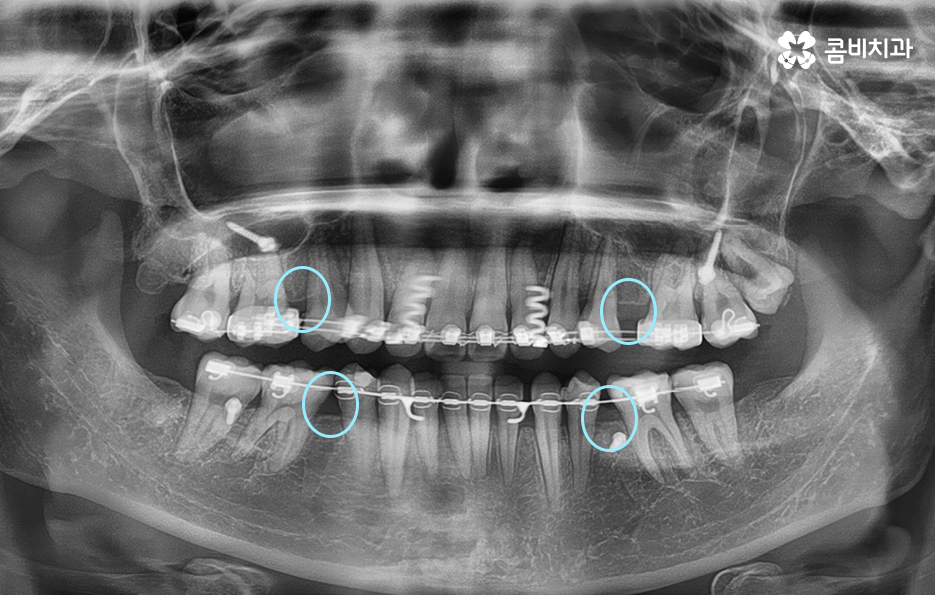

위 엑스레이 사진을 보시면 파란 원을 그린 부분이

발치를 한 부위이며 교정 기간이 경과함에 따라서

이 공간이 점점 메워지게 되고

가지런한 치열은 물론 돌출입도 개선됩니다.